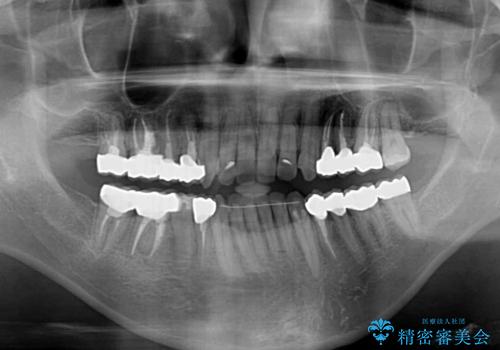

ワイヤー矯正を併用したことで、上顎前歯はあっという間に整いました。

補綴治療にあたり、痛みのある歯に対して根管治療を行うこととしましたが、処置が必要な歯が多かったため、期間を要しました。

補綴治療中に前歯のデコボコが戻ってしまったため、補綴治療後にインビザラインを1セット追加して仕上げました。